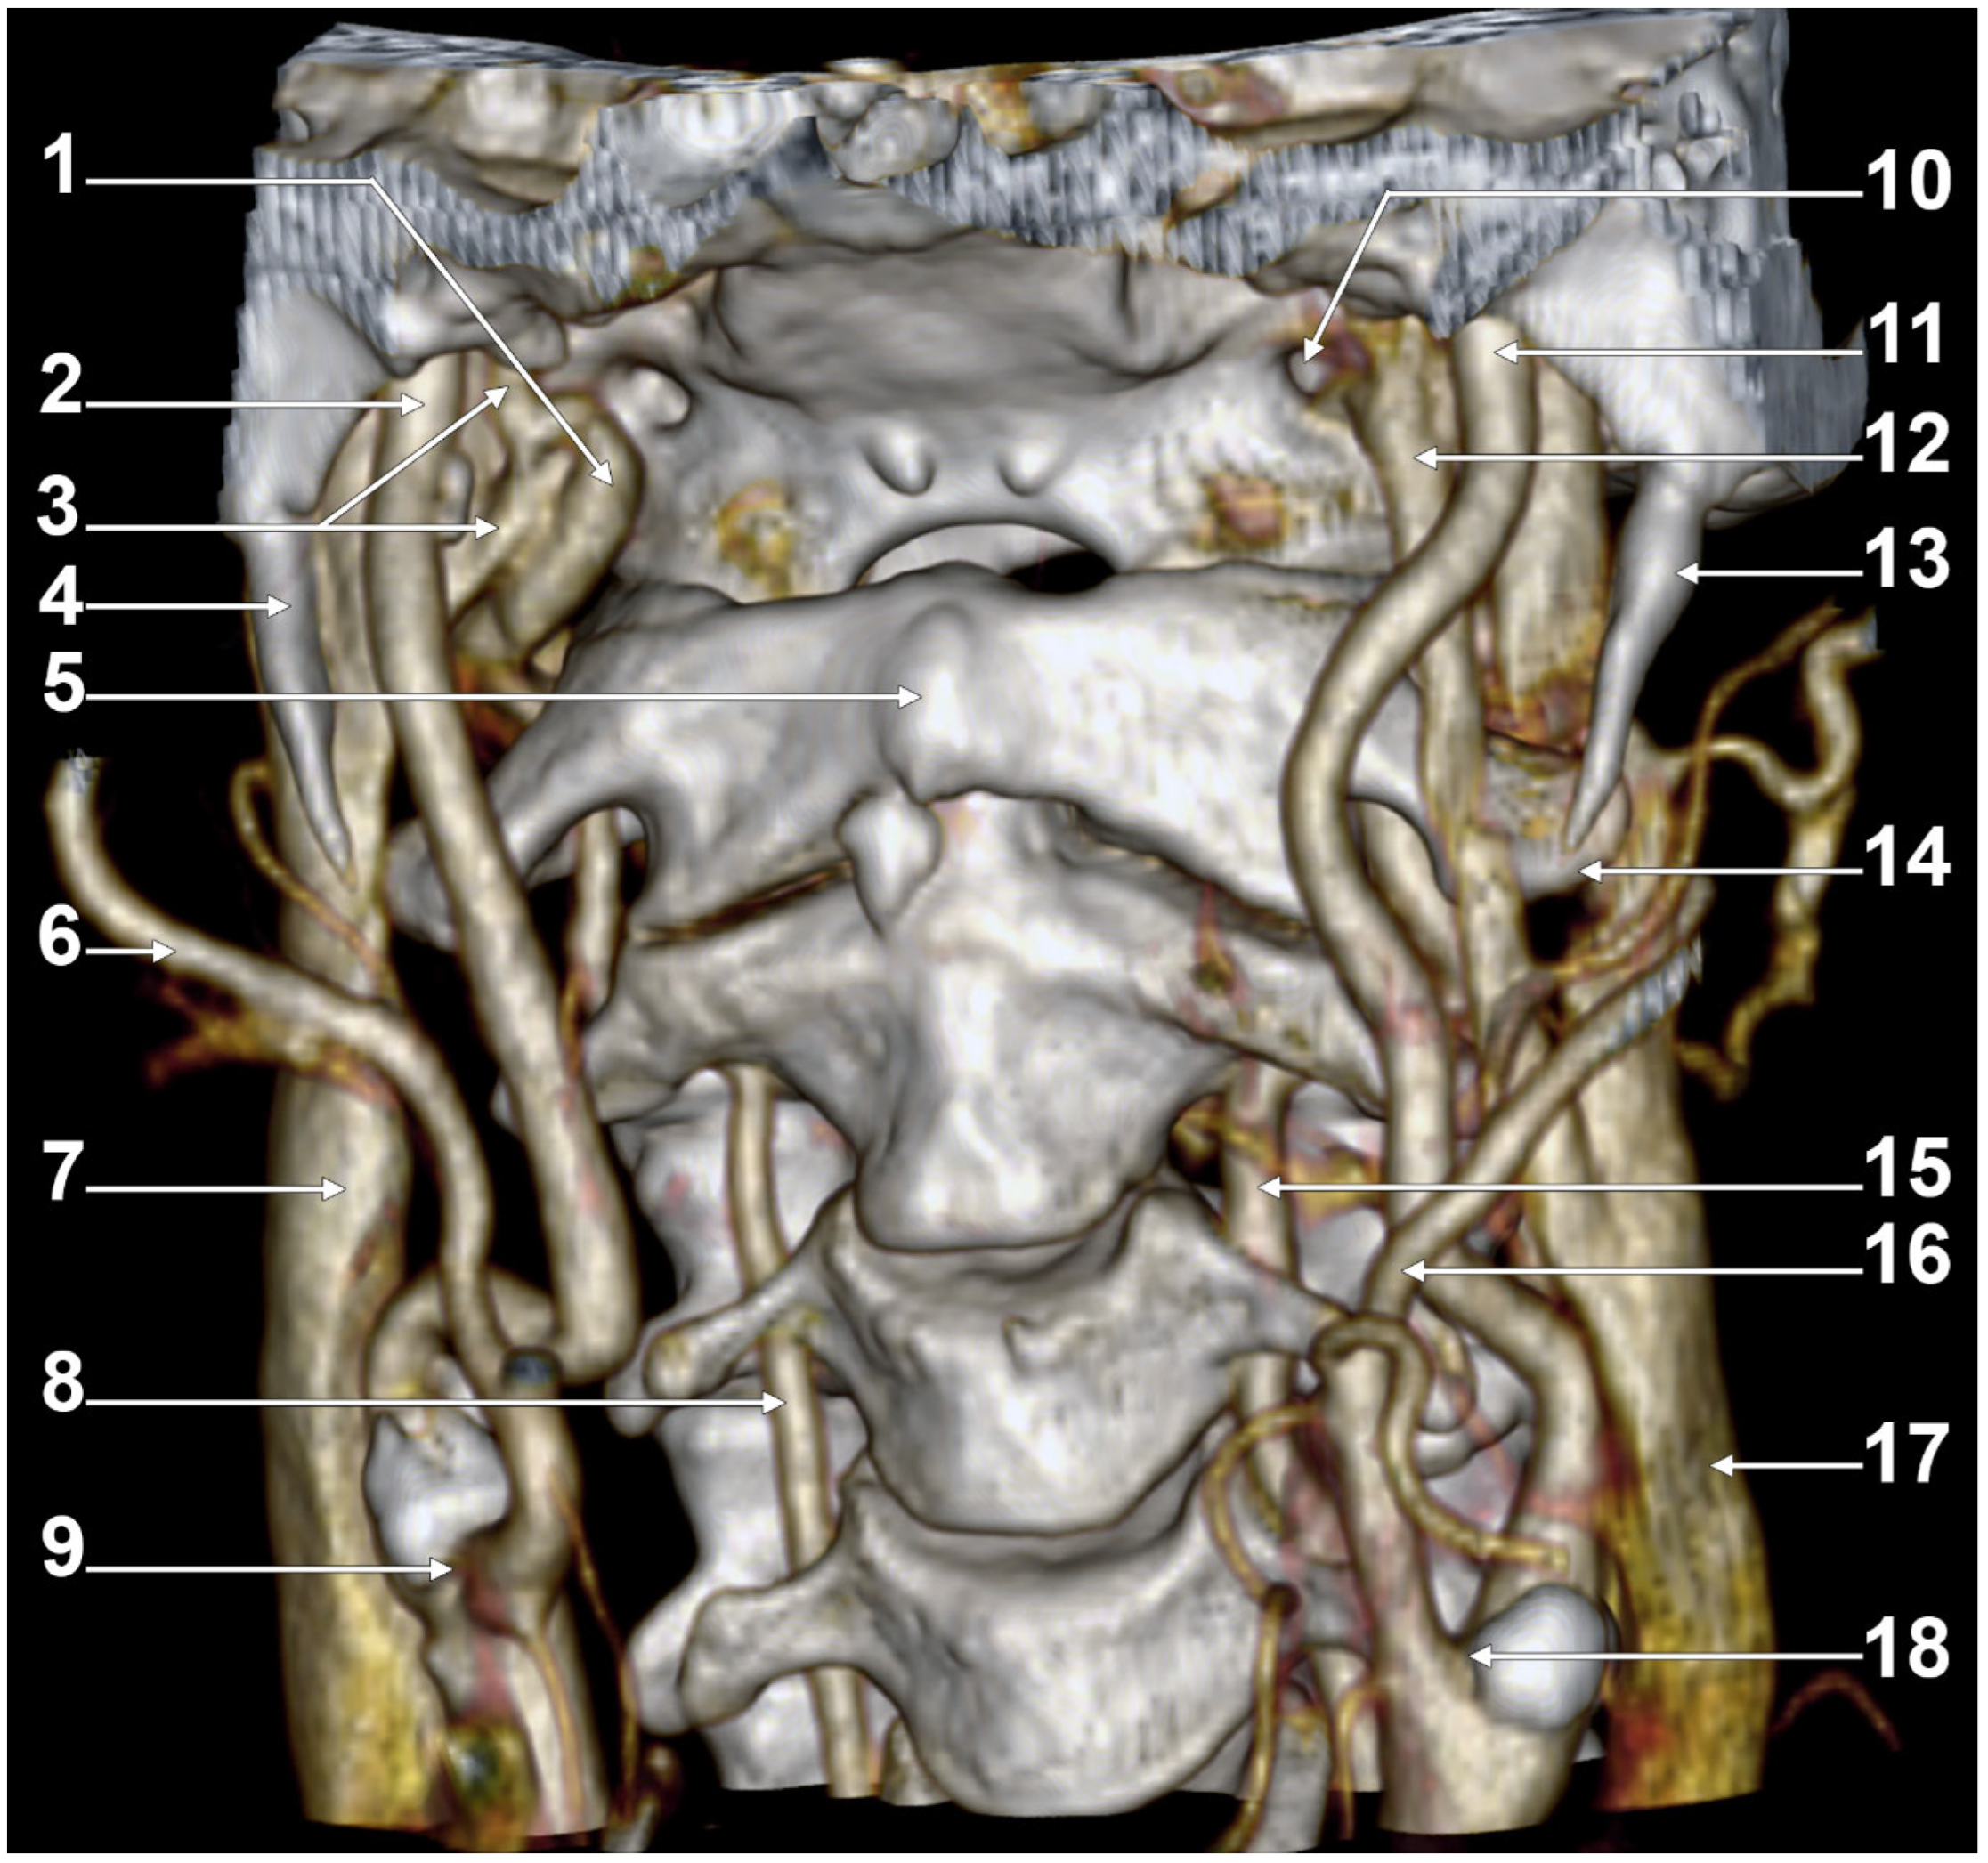

We present here a case with bilateral long IPSs (Figure 7 and Figure 8). The novelty lies in the fact that both the long IPS and the IJV were pinched within the C1/SP nutcracker. This is because, on the one hand, the stenosis of the IJV determines different neurological deficits, discussed elsewhere in this paper, and, on the other hand, a compressed IPS could not be of use as an endovascular passage when it is compressed into a nutcracker. Specific documentation of IPS compression between the SP and atlas appears to be either very rare in the literature or potentially underreported. During an anatomical study of the archived angioCT file of a 63-year-old male case, bilateral long IPSs were found. The right one was 1.25 cm long, and the left one was 5.15 cm long. The right one had a diameter of 0.2 cm. The opposite one had a diameter of 0.32 cm. The right IPS was joined beneath the jugular foramen by the lateral condylar vein. The left IPS descended antero-medially to the left IJV. Both these veins were applied and compressed on the anterior side of the transverse process of the atlas. The two veins continued anterolaterally to the transverse process of the axis, and at 0.41 cm below that process, the IPS ended into the IJV. On both sides, the ICAs crossed anteriorly to the IPSs to enter the carotid canals. Therefore, the anatomic route of the IPS, the long IPS-to-IJV confluence site, and the diameter of the IPS are relevant in clinical procedures, such as cavernous sinus sampling, which requires catheterisation of both IPSs. Knowledge of the venous anatomy, including variants of the IPS and its branches, is crucial for the diagnosis and treatment of parasellar lesions.